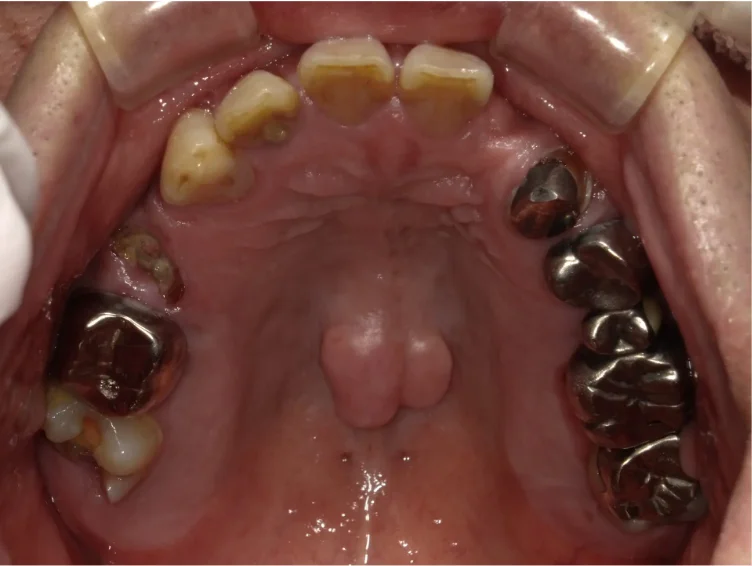

Before

After

ひどい歯周病で治すのが難しい、と言われた歯に歯周組織再生療法を行い改善(70代女性)

約1年 / 総額150,000円リスク・副作用:歯周病は一度改善しても、患者さんの心身の健康状態や歯磨き状況によって再発することがあるため、定期的なメンテナンスで維持できるようにしてくことが大切です。